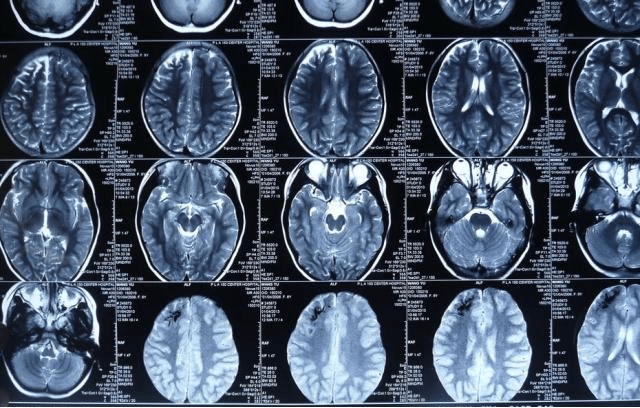

又称颅内三叉神经血管瘤综合征。主要表现为三叉神经分布区的微静脉畸形;脑膜静脉畸形,脑实质部分发育延迟;眼球内静脉畸形引发的青光眼,甚至眼球肿大,形成牛眼症;上颌骨和鼻骨血管畸形所致的骨骼连续增生,形成患侧的颅颌面骨膨胀,隆凸,牙颌骨发育畸形;患者可有不同程度的感觉神经异常,运动神经异常,如:肌肉不协调,癫痫,智力障碍甚至夭折。